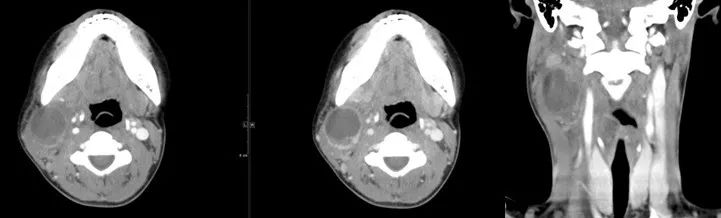

15 多间隙受累

(1)左下后牙疼痛11天余,颈部肿胀10天。

(2)右侧颌面部弥漫性肿胀1月余。